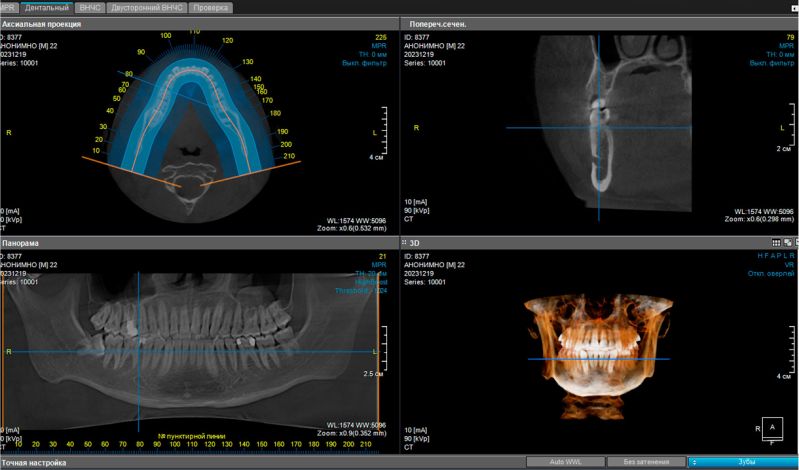

Диагностика зубов и челюстей

Компьютерная томография (3D) и панорамная зонография зубочелюстной системы обеспечивают детальное и чёткое изображение всех зубов, челюстей и прилегающих структур лицевого скелета. Это позволяет провести точную диагностику состояния челюстно-лицевой области.